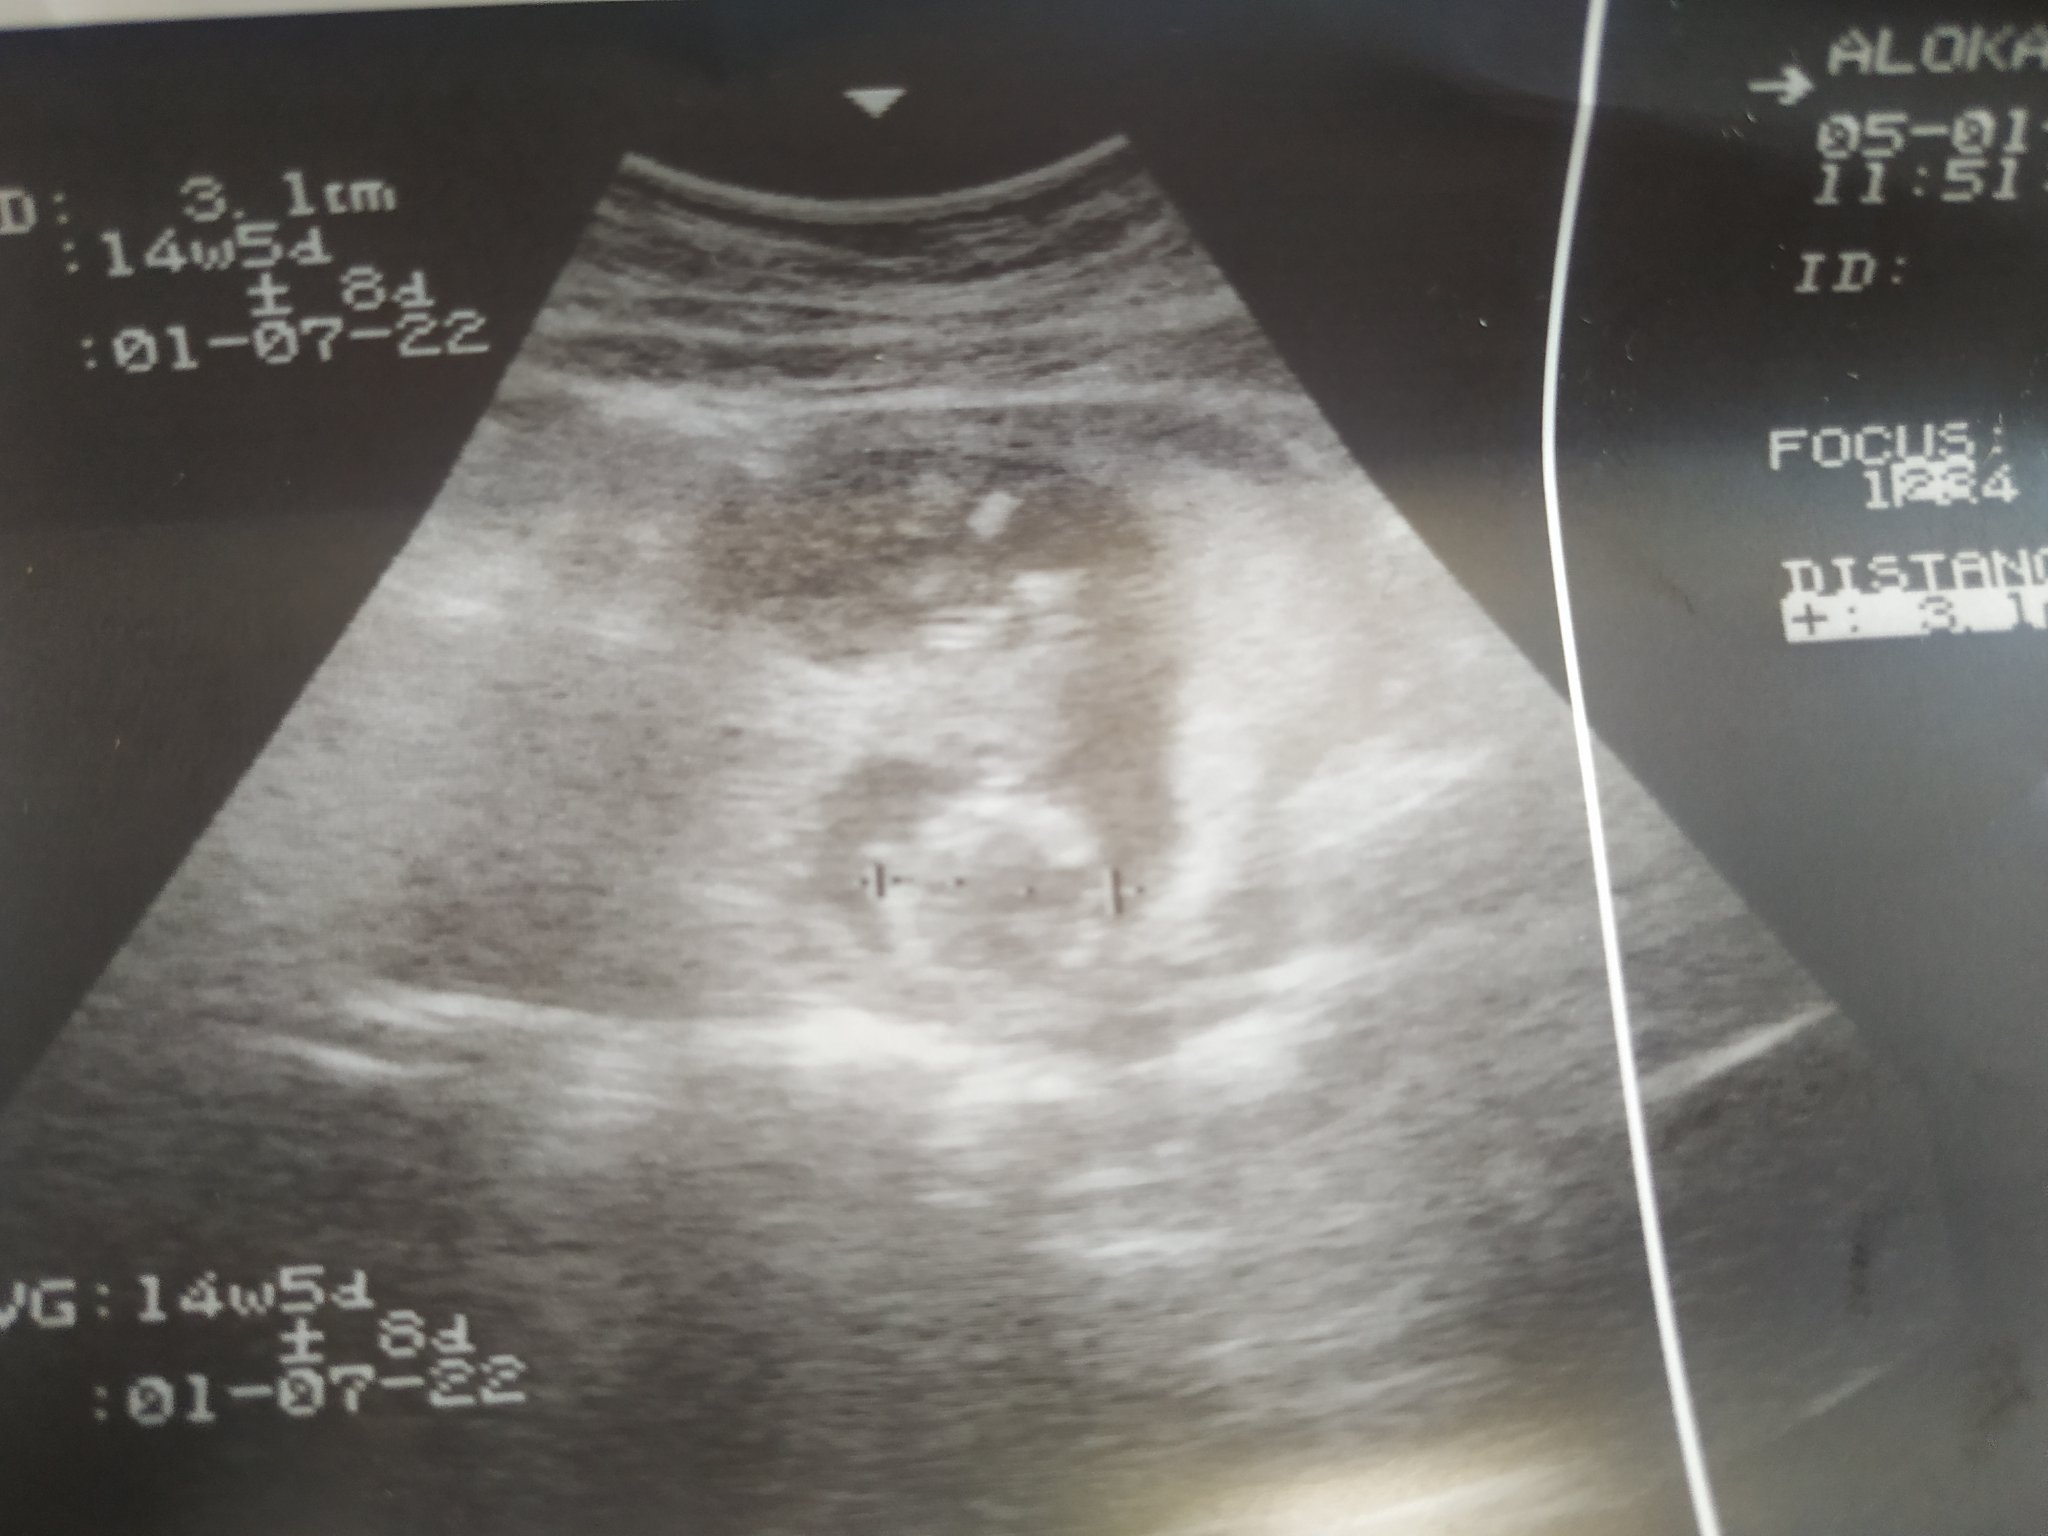

Как мога да определя датата на термина, когато цикълът ми е нередовен?